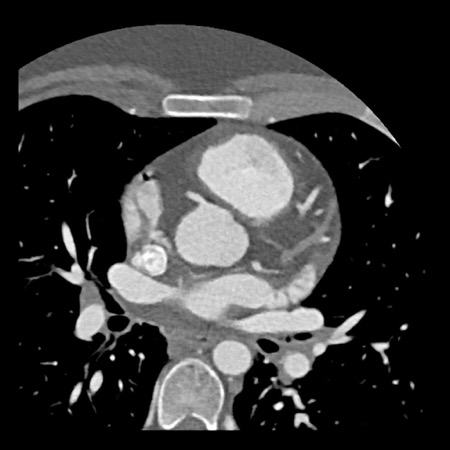

case 4 – CAD-RADS 3/P1/I+ thrombus left ventricle

The findings are:

- Moderate (50-69%)

stenosis in the proximal LAD caused by a non-calcified plaque. - Variant of

sinoatrial (SA) nodal artery. The artery usually arises from the RCA as a second

branch after the conus artery, however in this case it arises from the LCX,

courses behind the aorta, anastomosing with the right atrium and with a small

branch supplies the SA-node of the heart. - Thrombus in the

apex of the left ventricle. - CTP was performed

in this patient. CTP showed a perfusion defect at stress imaging in the

territory of the LAD (I+), at rest no perfusion defect was visible.

This patient classifies as CAD-RADS 3/P1/I+, which means

this patient requires further investigation.